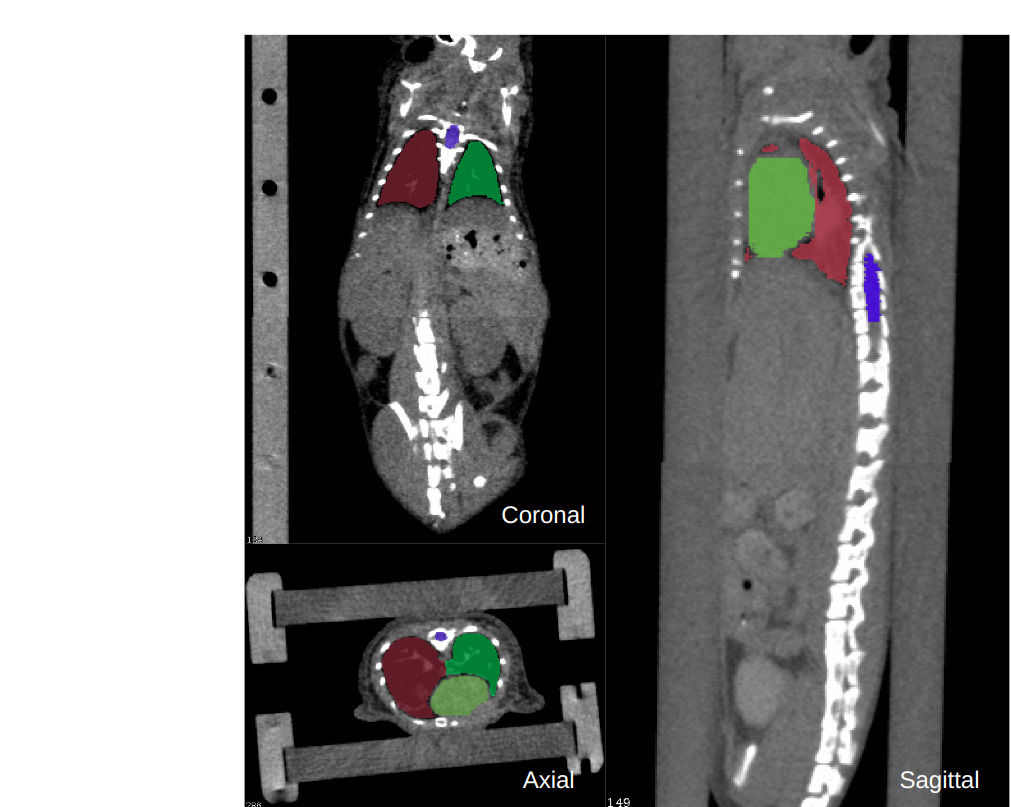

We separate the segmentation tasks into supported classes and zero-shot classes. The supported classes are the classes that have enough training data with annotations with which we can train VISTA3D to perform automatic segmentation. We curated an index list for supported classes and trained the automatic head to accept the index as the prompt and output a binary segmentation for the class. For zero-shot classes, the segmentation is only supported by VISTA3D interactive branch, which accepts user click points on 3D space. The interactive segmentation also works for supported classes. To train such a model, we curated a large dataset containing 11454 3D CT scans, generated pseudo labels from TotalSegmentator model [7] and supervoxels using SAM pre-trained weights [24]. A stage-by-stage training recipe is used to train interactive and automatic separately.

Supervoxel generation The vast majority of SAM’s zero-shot capabilities come from this large-scale supervised training on its 11 million diverse and fully annotated images [24]. Those annotations helped SAM learn how humans perceive an object, and become the image segmentation foundation model. However, the manual labels or pseudo-labels in 3D CT can only cover around one or two hundred of classes. We empirically found that this level of class diversity is not enough for the model to achieve SAM-like zero-shot ability in 3D. To solve this problem, most works decided to finetune SAM pretrained ViT checkpoint on 2D medical data to inherit this zero-shot ability, which inevitably limited the adaptability to 3D images. Here we propose a novel method to distill the image understanding ability from SAM by generating 3D supervoxels from 2D SAM feature maps. The algorithm is shown in Alg. 2. We perform a 3D supervoxel algorithm on the upsample SAM feature embedding, which is generated slice-by-slice in three views. An example of generated supervoxel results is shown in Fig. 2. We generate supervoxels for all 11454 CT scans and use them to train our interactive branch, and this gave VISTA3D zero-shot capabilities. SegVol [14] used a similar idea but the supervoxel generation is based on graph-cut, which is still on low-level image features. Instead, VISTA3D achieved better zero-shot performance through distilling knowledge from SAM.

In this section, we test the zero-shot ability of VISTA3D. We compare with MedSAM [28] and SegVol [14] as they showed the best interactive performances in 2D and 3D separately. For the MedSAM baseline, we adopt the 3D inference pipeline via a series of 2D slices as described in [28]. For segmentation targets that are larger than 10 voxels, tight bounding boxes for each slice were generated to simulate user-provided prompts. Each bounding box is considered the same annotation effort as two-point prompts in our evaluations. For the SegVol baseline, the default settings [14] are evaluated using a positive point with three pairs of positive and negative points (7 points in total), as well as the zoom-out-zoom-in inference strategy. For VISTA3D, We mimic user annotations to perform iterative point clicks. The first point is sampled at the foreground center, then the next point will be randomly sampled from the largest connected false positive or false negative region, which has a larger area size. We evaluate the performance of 4 novel external datasets. 1) the murine dataset [29] includes 140 scans with 4 annotated mouse organs: heart, left lung, right lung, and spinal cord. The CT scanning protocol and organ shapes are quite different to humans as shown in Fig. 3. 2) the C4KC-KITS (kidney tumor, 210 scans) dataset [18], the Adrenocortical Carcinoma (adrenal tumor, 53 scans) dataset [30, 13], the Hepatocellular Carcinoma (liver tumor, 105 scans) dataset [31, 13]. The results are shown in Fig. 3. The results show the superior performance of VISTA3D in both accuracy and reduced annotation efforts. VISTA3D trained without supervoxel (VISTA-NoSupervoxel) is also shown in the figure, and the results showed the importance of supervoxel for the zero-shot ability.